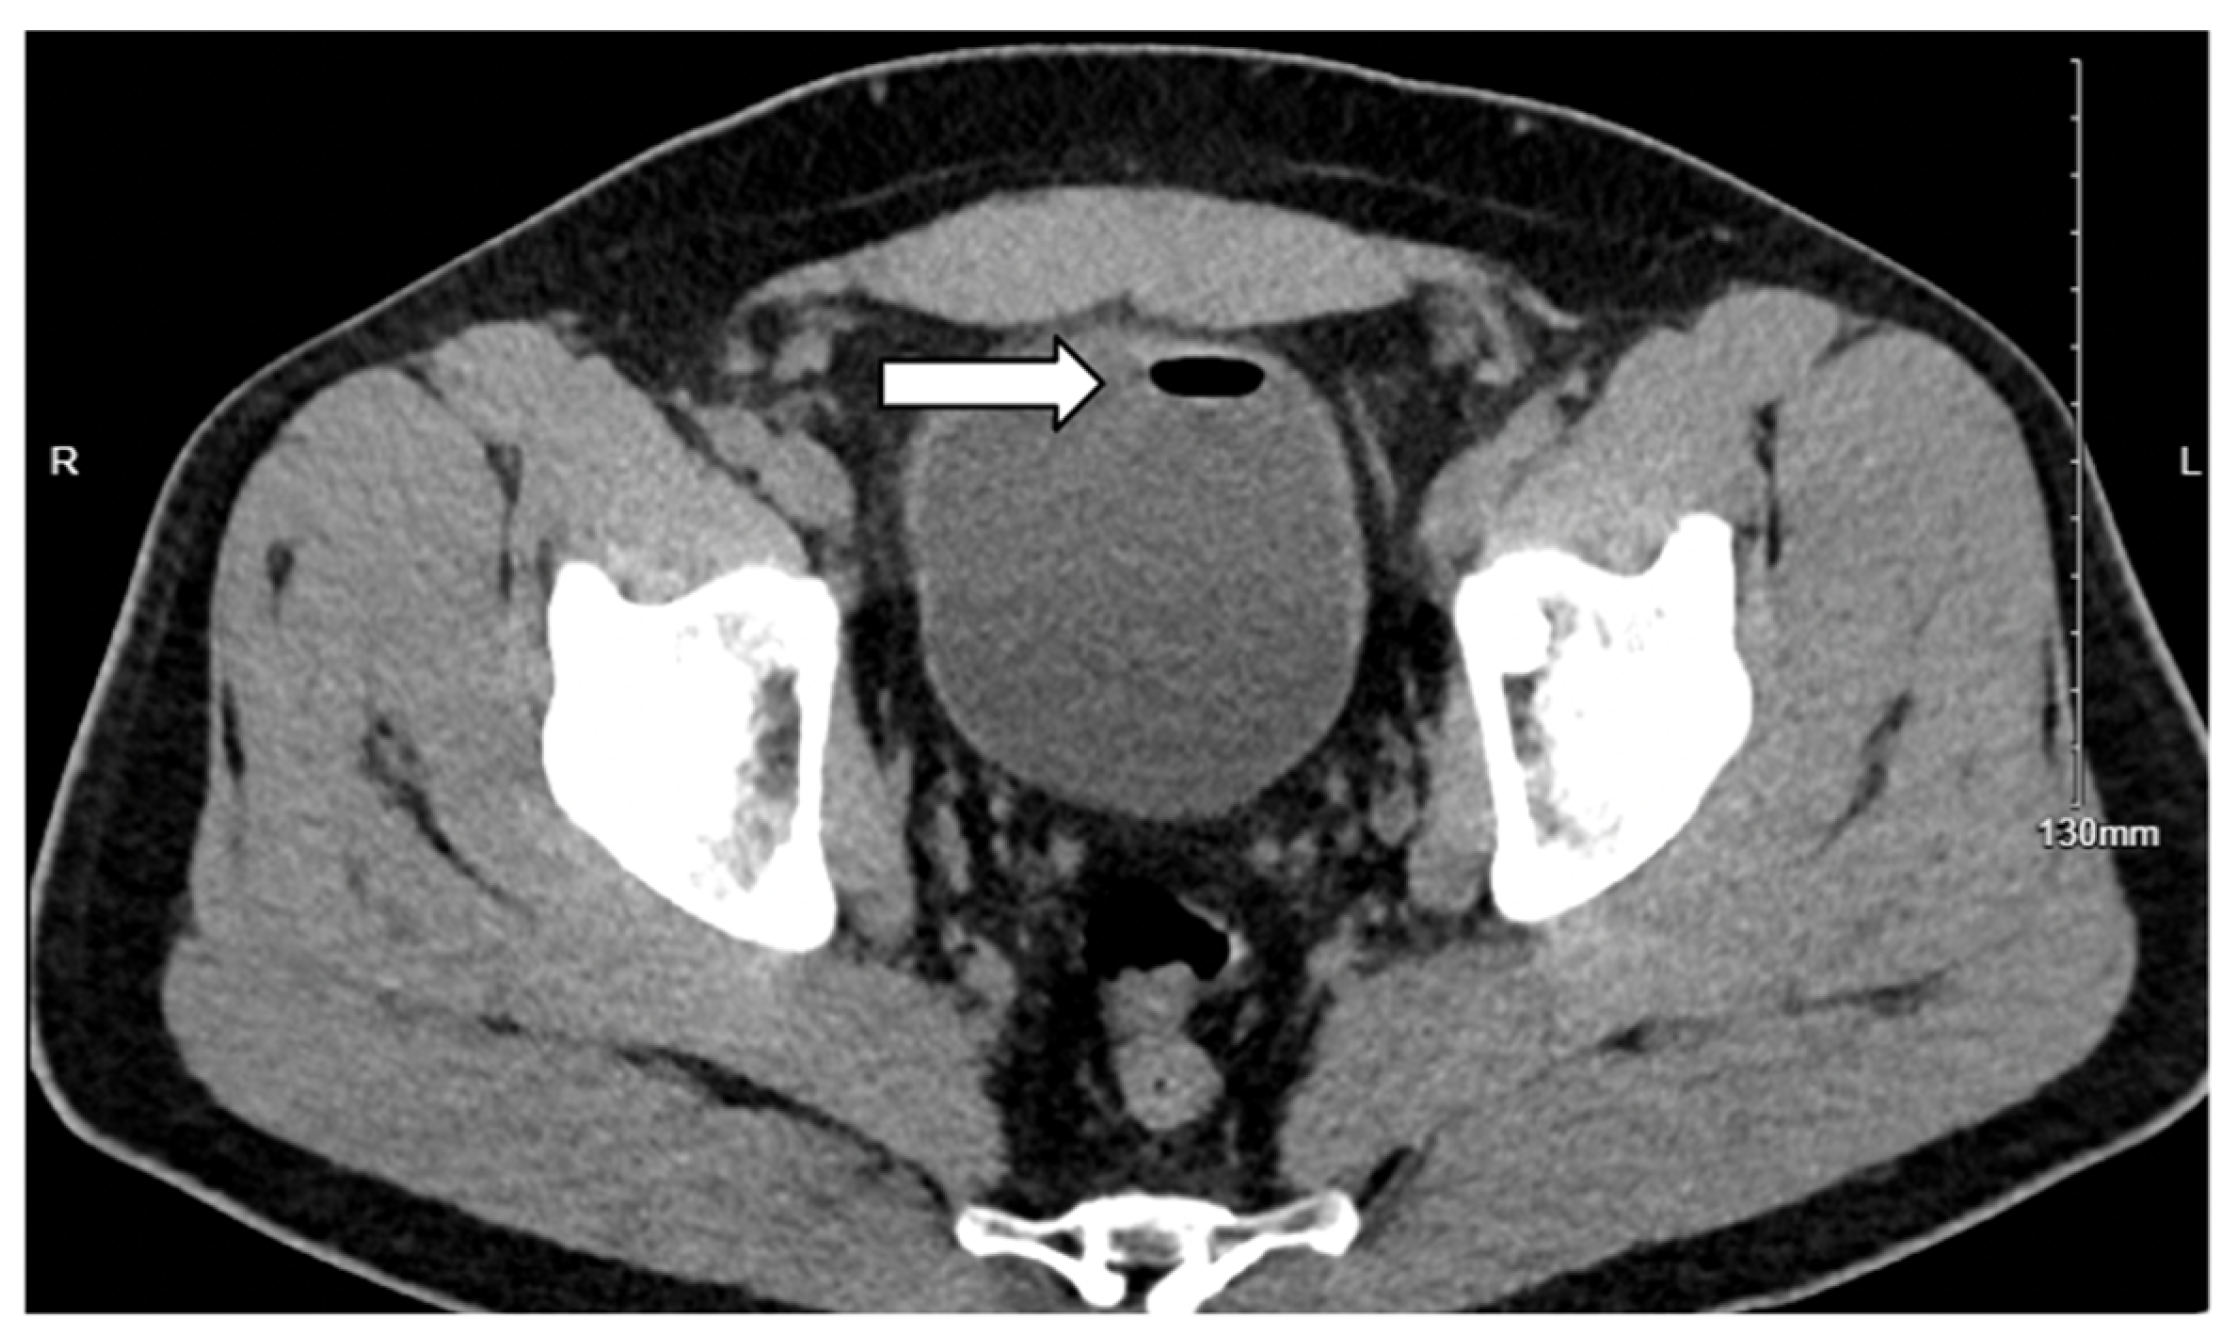

3.1. Case 1